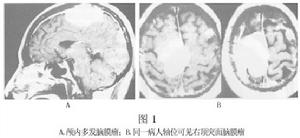

依靠傳統的頭顱平片、腦血管造影和腦室造影診斷多發腦膜瘤是比較困難的。當今,套用CT和MRI便可比較容易地確診顱內多發腦膜瘤(圖1)。

注意與單發的腦膜瘤相區別,MRI的套用有助於多發腦膜瘤的鑑別診斷,尤其是其矢狀位及冠狀位強化掃描可以清楚地顯示顱底部位的腦膜瘤,並能清楚地顯示腫瘤基底,有助於區別分葉狀的腫瘤與基底相鄰的多發腦膜瘤。

CT或MRI檢查,CT平掃可以很容易地發現那些體積較大,發生於大腦凸面、矢狀竇旁、腦室內及後顱窩的腦膜瘤,但發生於顱底的、體積較小的腫瘤不易發現,因此強化CT掃描是有必要的,尤其是患者的臨床症狀比較複雜臨床與影像學不一致的情況下。多發腦膜瘤在CT或MRI的表現與單發腦膜瘤的特徵相同。CT可以清楚地發現腦膜瘤的鈣化,尤其在混合型或纖維型腦膜瘤較多見。CT還可顯示腫瘤的囊變及其四周腦水腫這種情況常常發生在富於血管的腦膜瘤。

在MRI的T1像上,差不多30%的腦膜瘤為低信號60%為等信號。T2像上腦膜瘤的信號不一致,約50%為等信號,40%表現為高信號。注射對比劑對提高圖像的分辨能力是很有幫助。